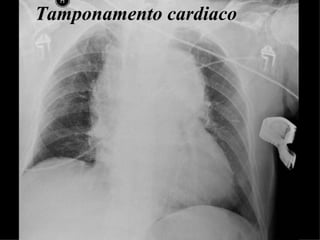

Tamponamento cardiaco

Pneumotorace